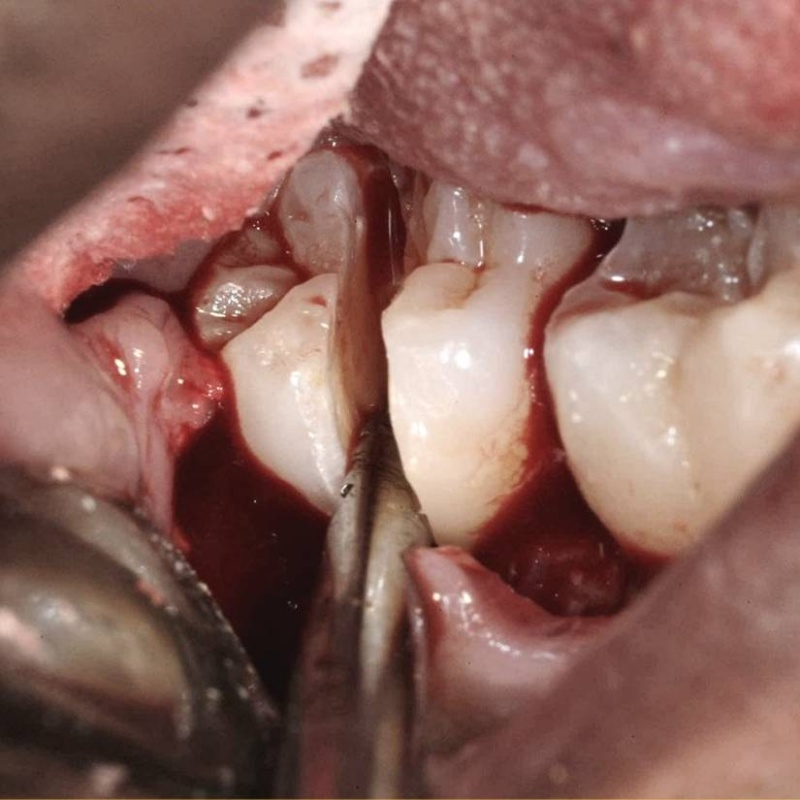

You and your patients will benefit from this practical video! Almost every dentist does some oral surgery, but very few have had significant education in surgical procedures. Karl and Gordon have made a practical, easily understood, step-by-step live video showing necessary concepts, techniques, and instruments needed for oral surgery in your practice. Frequently needed techniques are emphasized, including use of luxators, inter-radicular bone removal, mesial and distal troughing, sectioning roots, and buccal bone removal. Receive many tips on how to make routine surgery faster, easier, and more enjoyable.

- Intra-radicular Bone Removal

- Mesial and/or Distal Troughing

- Sectioning 1st and 2nd Molars

- Patient Surgery